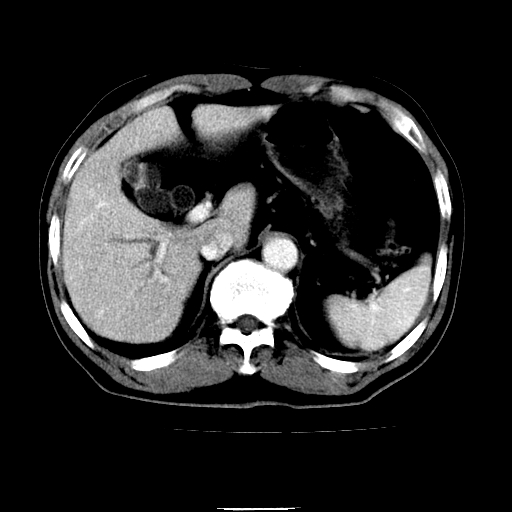

以下是引用chenqiong在2010-3-25 20:56:00的发言:[br]1、胆囊炎,胆囊息肉[br]2、肝内胆管及胆总管扩张,胆总管下端结石[br]3、十二指肠乳头旁憩室

以下是引用zxl51642在2010-3-26 10:47:00的发言:[br]胆囊炎,胆囊息肉,胆总管扩张,但未看到明显肿块,肝内胆管扩张不像恶性,炎性狭窄或阴性结石可能吧,建议mrcp,右肾小囊肿